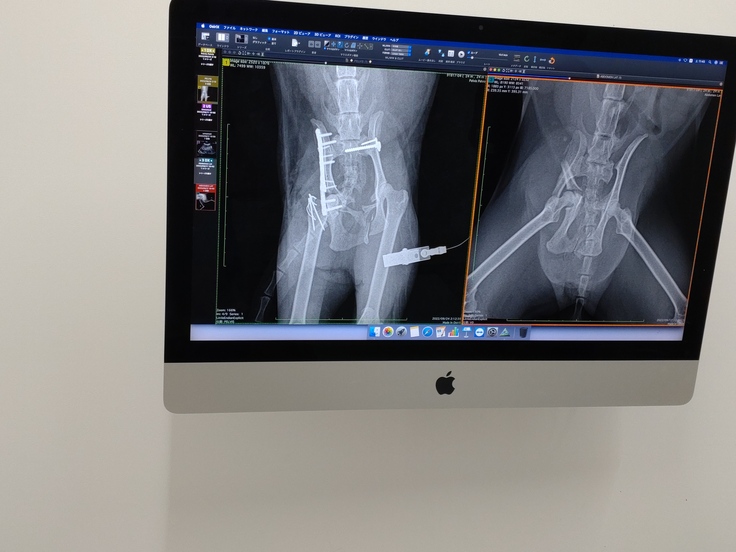

2022/9/18 検査結果と面会を兼ねて病院へ。そこでわかったのが左骨盤骨折と右骨盤のズレとの事でした。点滴を受けて300㌘増え、ご飯とちゅ~るを自力で食べていると先生が嬉しそうに教えてくれました。

2022/9/23 骨折を放置してしまうと、折れたままです固まってしまうため、早めの処置が必要な為、手術していただきました。

左の骨は3箇所以上にに折れているので、薄い板のようなもので補強し固定していただきました。

複雑骨折しているようで、ネコちゃんの薄い骨では固定しきれないところもあるようですが、あまり影響なく過ごせるそうです。

右はズレているのを元の位置にネジで固定していただきました。